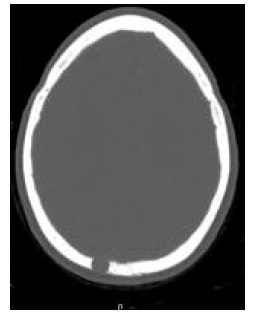

Para estudo da lesão solicitou-se uma tomografia computorizada crânio-encefálica (TC-CE), a 22.10.2018, que demonstrou uma lesão lítica da calote craniana na extremidade superior da escama occipital para-mediana direita, com cerca de 11 a 12mm de diâmetro transversal, associada a erosões completas das tábuas interna e externa do crânio e do espaço diplóico (Figura 2). Verificou-se também a presença de um pequeno componente de partes moles epidural junto a esta lesão lítica, em contacto com o contorno direito do seio longitudinal superior.

Figura 2 TC-CE mostrando a lesão lítica intradiploica na extremidade superior da escama occipital para-mediana direita.

Em TC-CE, o meningioma típico corresponde a uma massa extra-axial bem definida, de contornos regulares, por vezes com calcificações intralesionais, isointensas com o parênquima e associadas a hiperostose no local de inserção e com captação intensa de contraste.13

No caso descrito, a doente tinha 58 anos e não apresentava história de trauma significativo ou fratura craniana antiga. Não se verificou a presença de alterações neurológicas atribuídas à lesão; contudo, ficou patente a inespecificidade dos sintomas que pode estar presente numa fase inicial. Apresentava os rastreios oncológicos atualizados, de acordo com a faixa etária e com resultados normais. A investigação laboratorial não revelou alterações. Na radiografia, a lesão apresentou-se como uma imagem de morfologia arredondada e hipertransparente, traduzindo a sua natureza osteolítica. A TC-CE confirmou a lesão lítica na calote craniana, associada a erosões completas da tábua interna e externa do crânio e do espaço diploico. Na RM-CE, a lesão exibia discreto componente epicraniano, pequeno extra-axial intracraniano e aparente base de implantação dural, mas sem dural tail. A doente foi submetida a craniotomia para exérese do tumor e cranioplastia com material sintético. O pós-operatório decorreu sem intercorrências. A doente mantém seguimento em neurocirurgia, onde fará reavaliação imagiológica posterior no sentido de confirmar a ausência de recidiva.